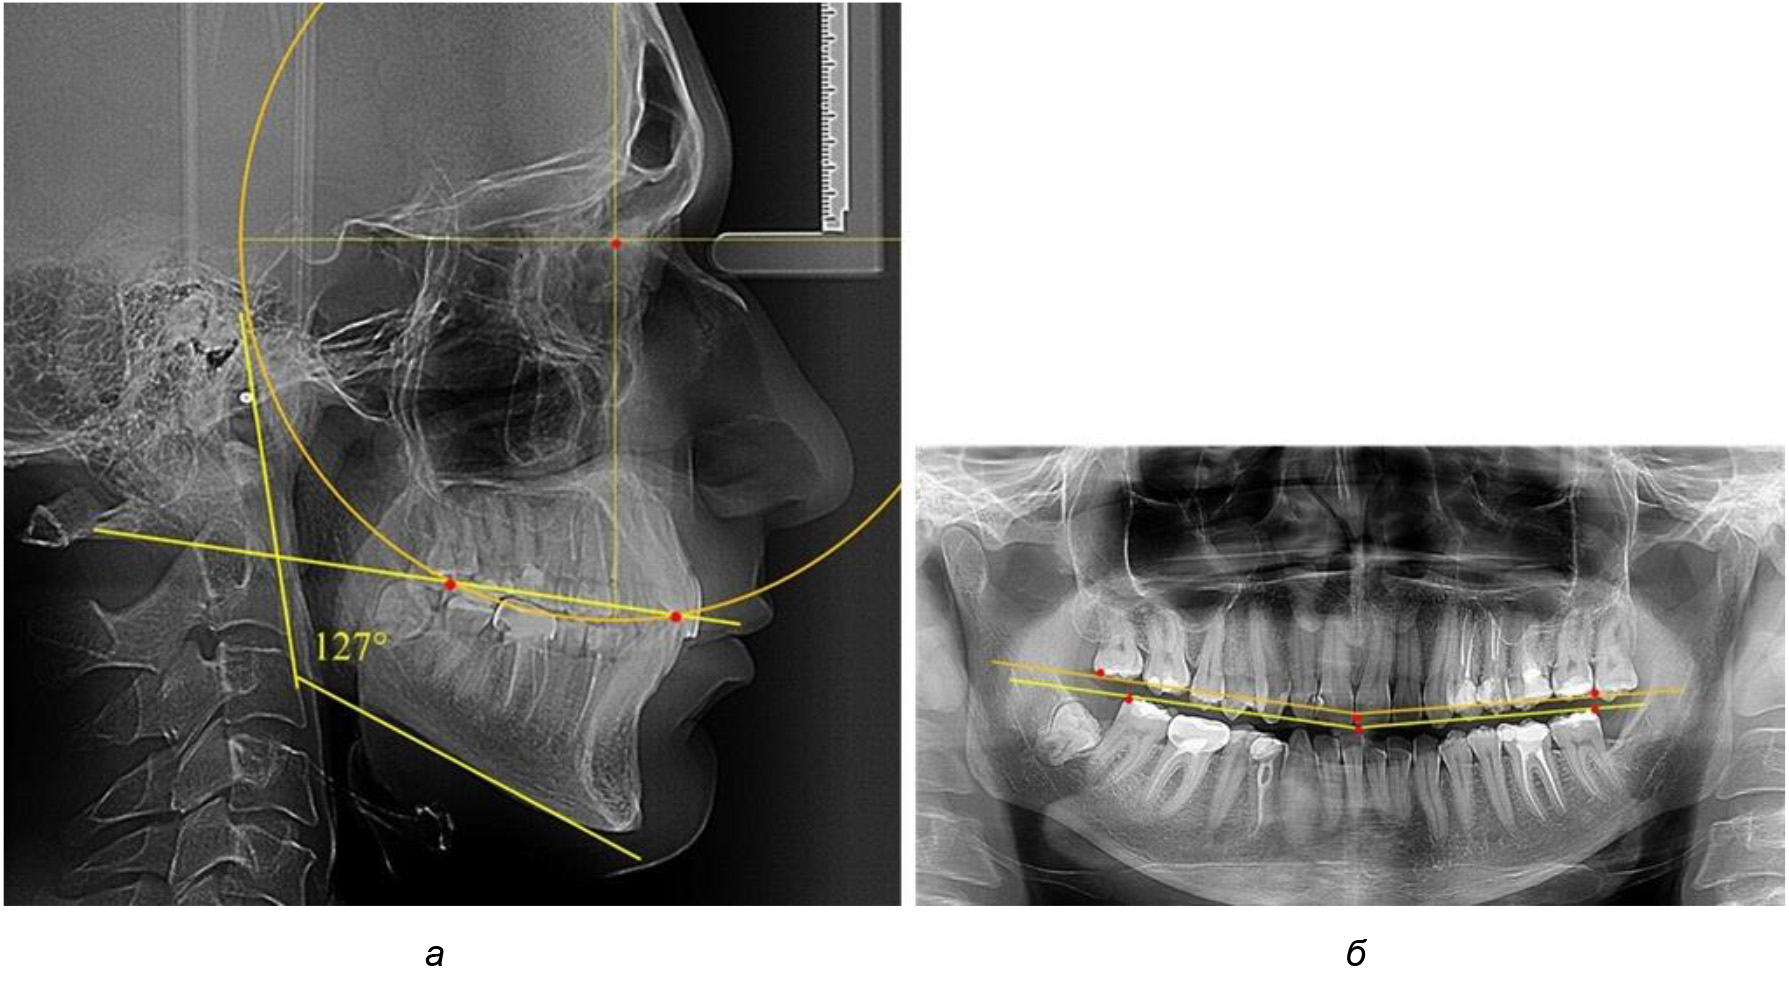

Рис. 1. Метод определения кривой Spee на ТРГ (а) и на ОПТГ (б)

При анализе латеральных ТРГ устанавливали реперный окклюзионные точки в переднем и боковом отделе. Передняя точка устанавливалась на режущем крае нижнего медиального резца, которую в клинике ортодонтии обозначают как vPOcP. Дистальная точка второго нижнего моляра обозначалась как hPOcP. Измеряли расстояние между окклюзионными точками, что определяло сагиттальный размер окклюзионной линии. Использование программ PowerPoint позволило проводить окружность, проходящую по линии смыкания зубов через окклюзионные точки. Измеряли радиус окружности. Учитывая вариабельность размеров окклюзионной линии и радиуса окружности, определяли относительный показатель через отношение радиуса круга к длине сагиттального размера окклюзионной линии. Глубину окклюзионной кривой измеряли от точки наибольшей выпуклости до окклюзионной линии (рис. 1). На ортопантомограмме (ОПТГ) также соединяли окклюзионные точки правой и левой стороны и измеряли глубину окклюзионной кривой от точки наибольшей выпуклости до окклюзионной прямой линии. Результаты глубины кривой Spee сравнивали по данным ТРГ и ОПТГ.

Деление величины радиуса круга к длине окклюзионной линии составило 1,623 ± 0,02. Таким образом, для определения радиуса окружности, соответствующей кривизне окклюзионного контура боковой ТРГ, необходимо измерить расстояние между передней и задней окклюзионными точками и последующим умножением полученной величины на число Фибоначчи (рис. 2).

Рис. 2. Особенности кривой Spee на ТРГ (а) и ОПТГ (б) у людей с признаками вертикального роста